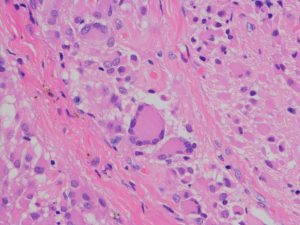

病理と予後

- 病理像では,好酸性の胞体 glassy eosinophilic cytoplasm を有する不整形の巨細胞の存在が特徴です

- 核は,多型で複数核 pleomorohic binucleate to multinucleate,クロマチンは粗,核小体が明瞭で神経節細胞様の大型のものもみられます

- 腫瘍細胞にはGFAP, vimentine, S-100が陽性で,巨細胞はNF, NSEなどが陽性となることがあります

- 血管増殖像はなく,核分裂もなく,組織の異型性に反して臨床的には良性腫瘍の性格を呈します

SEGAの病理像

基本的には,大きくて太った細胞 large plump cells で構成されます。gemistocytic astrocytesにています。

polygonal cells, ganglionic-like cells with a clear nucleoli, and plump large tumor cells resembling gemistocytic astrocytes

multinucleated giant cells

perivascular pseudorosettes, sweeping fascicles